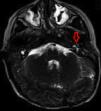

Acta Otorrinolaringológica Española Lipoma of the Middle Ear: An Unusual Presentation in a 6 Year Old Child

Lipoma of the Middle Ear: An Unusual Presentation in a 6 Year Old Child

Lipoma de oído medio: una presentación inusual en una niña de 6 años

Figures (3)